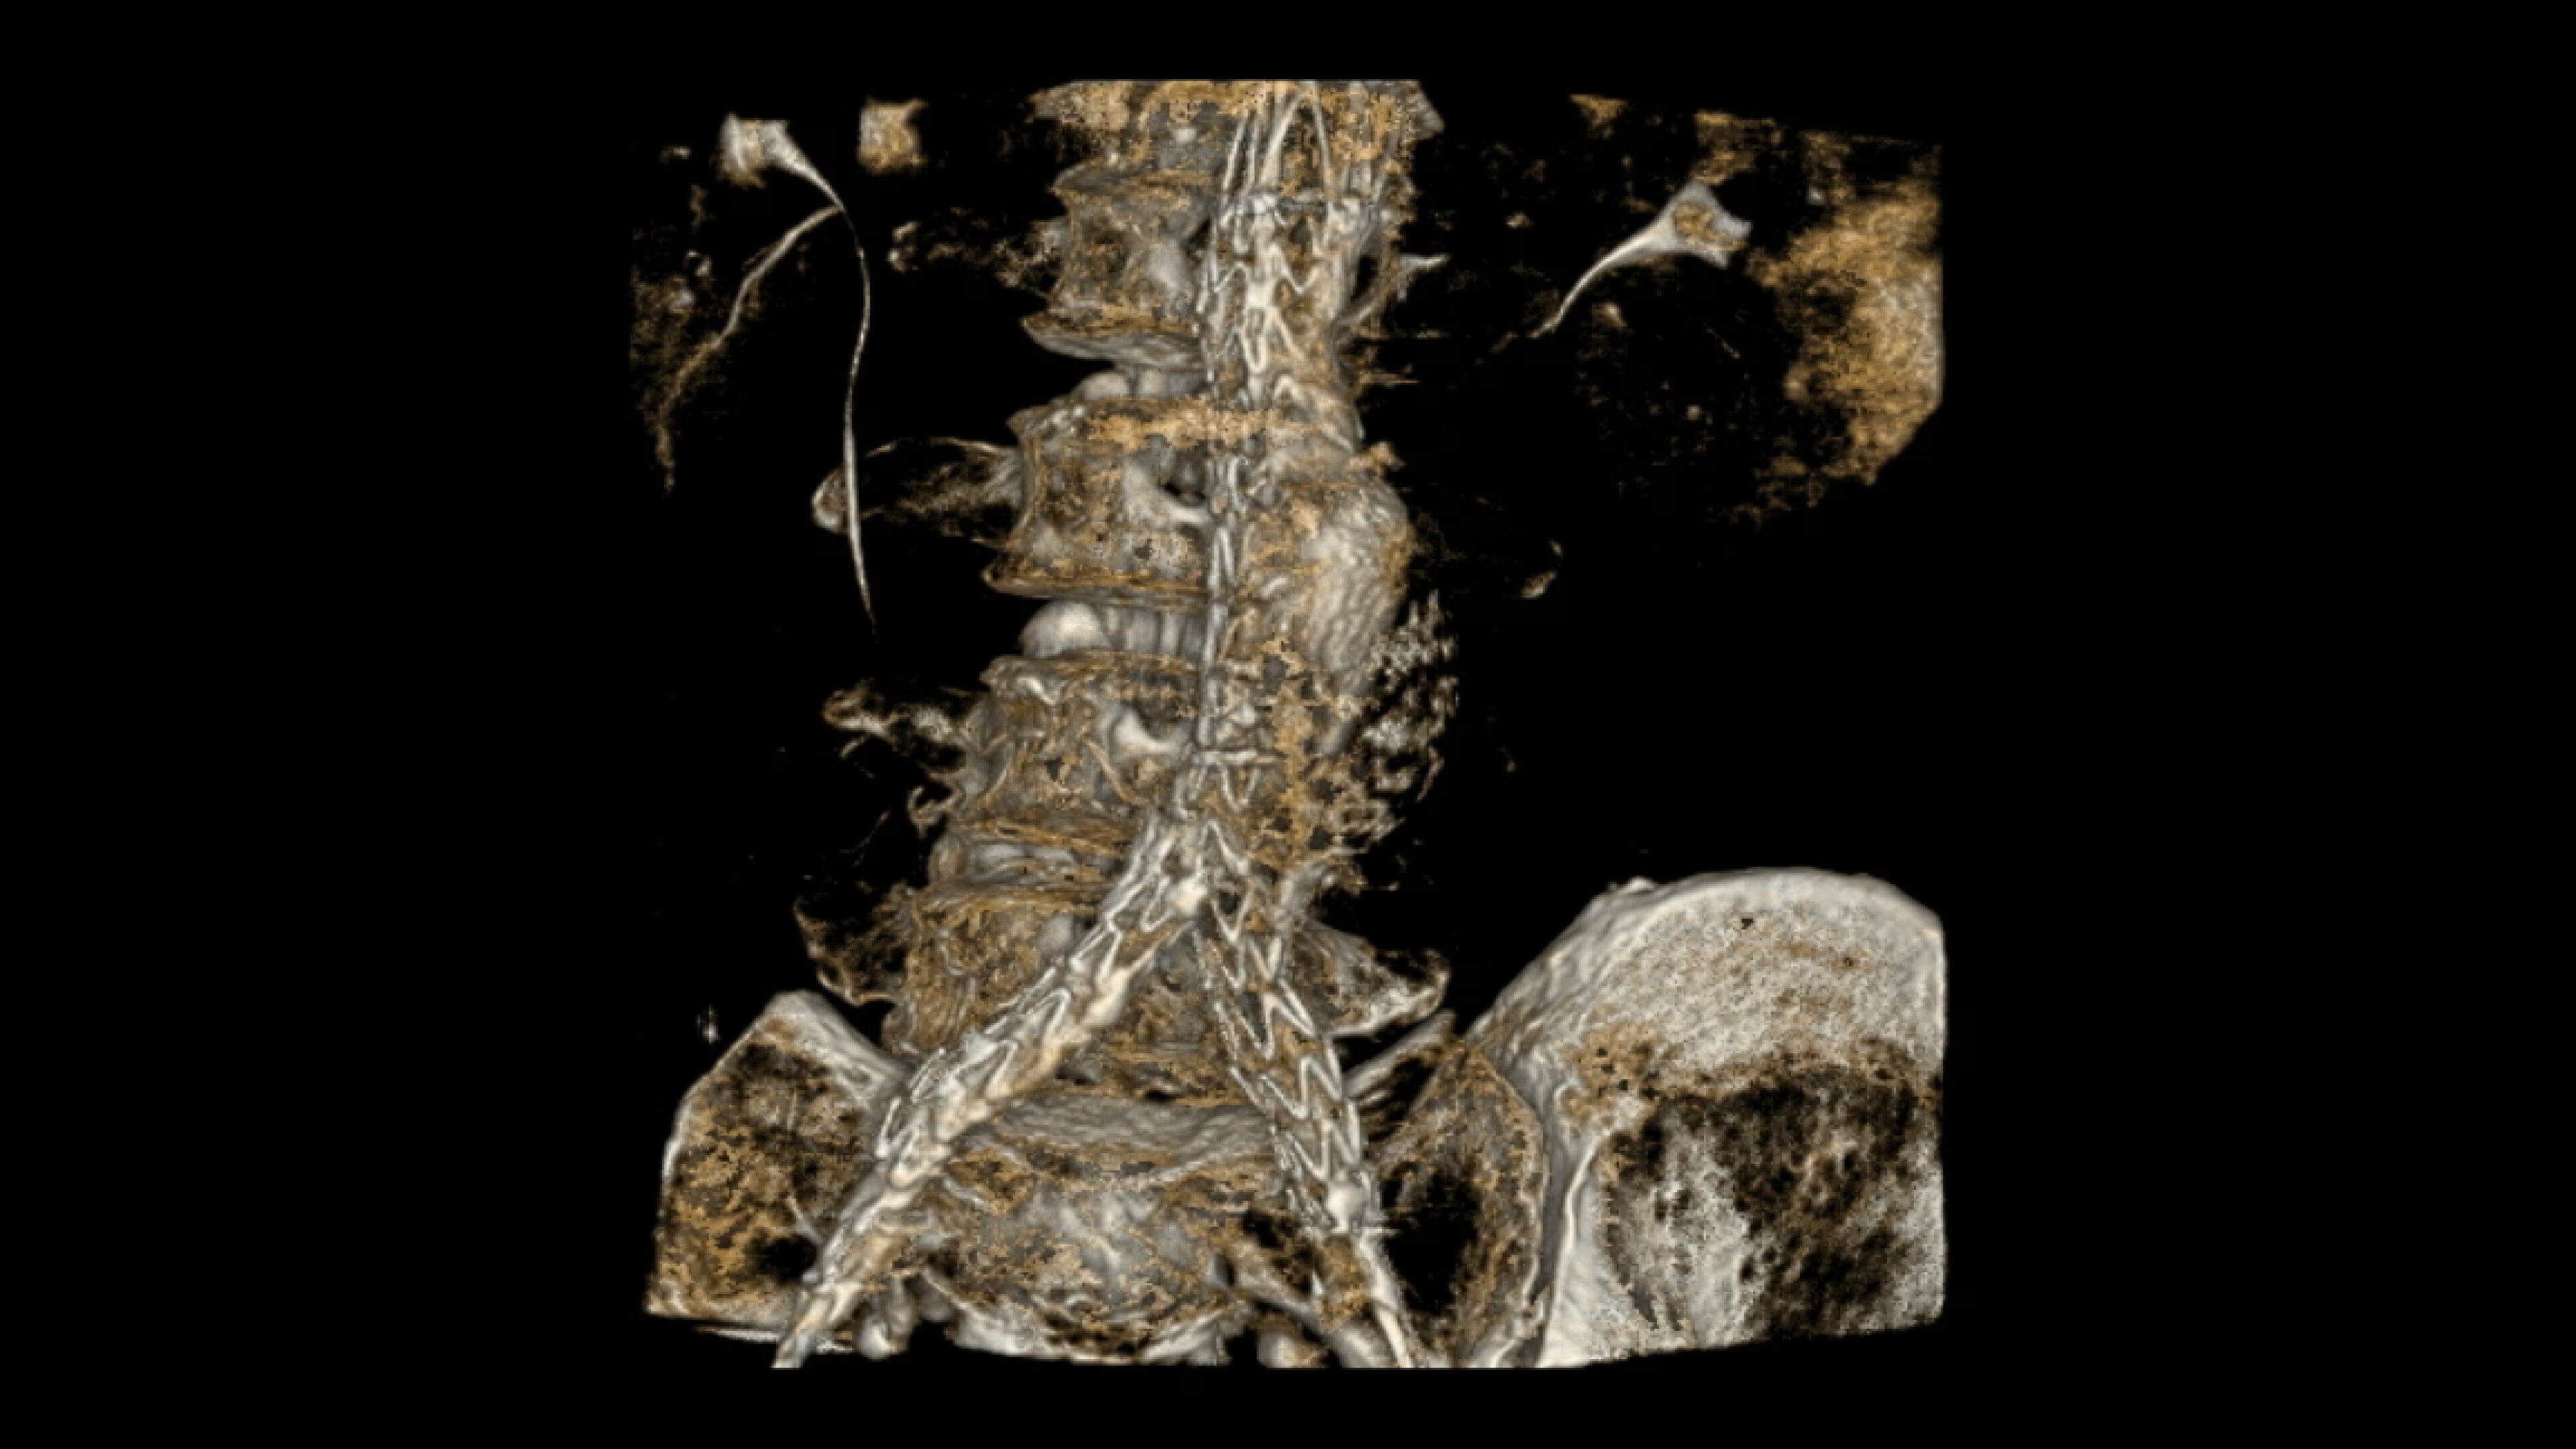

When visual confirmation during a procedure is desired, the

OEC 3D can provide 3D volumes with five perspectives.

Analyze CT-like images with the OEC 3D Volume Viewer which includes Multi-Oblique, Area Measure, Window Level/Window Width, rotate, zoom, and more for quick and comprehensive visualization.